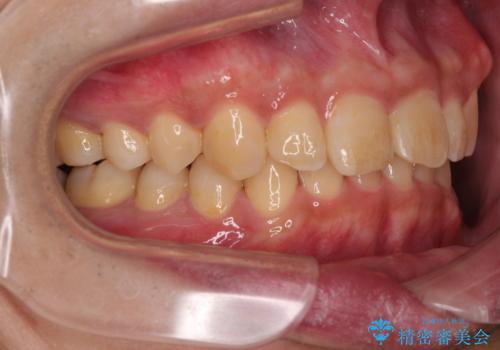

上顎歯列を遠心移動させたことで、前歯の叢生が解消されても前歯が前突することなく、左右ともに理想的な咬み合わせを達成することができました。